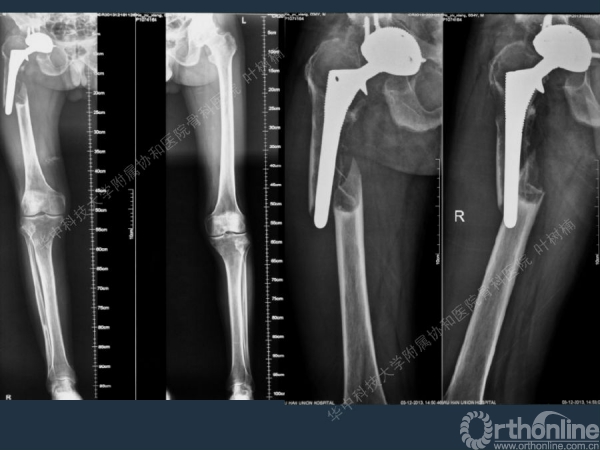

股骨侧翻修

髋臼缺损的处理